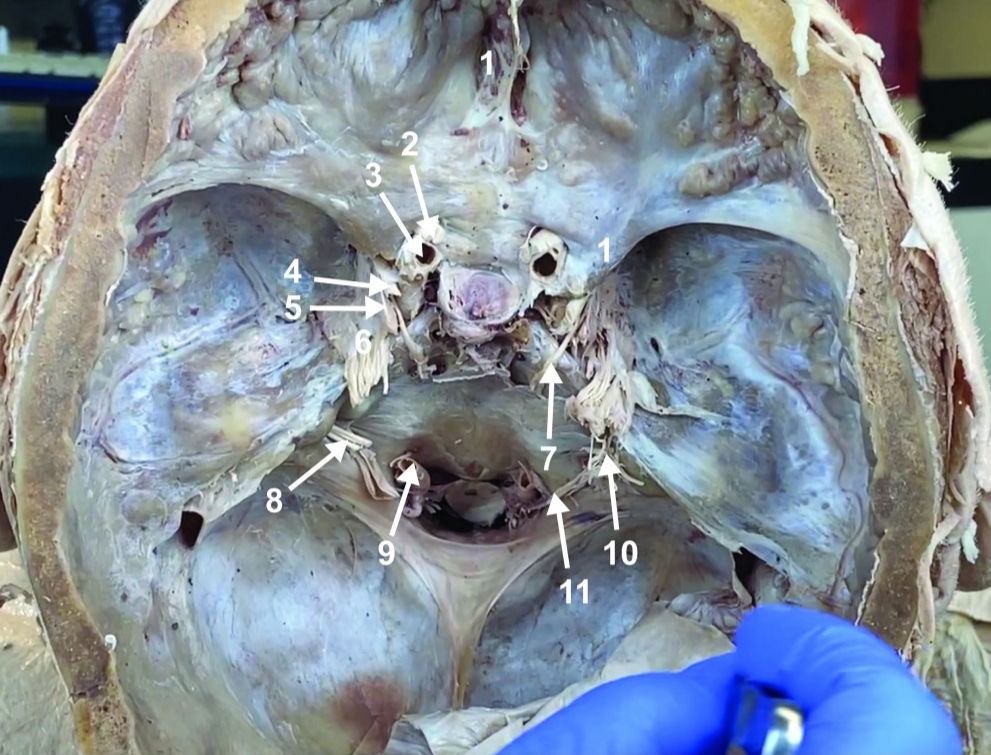

Foramen magnum

ID structure

Foramen ovale

ID structure

Foramen spinosum

ID structure

Cribiform plate

ID structure

Optic n. (CN II)

ID structure

Internal carotid a. (ICA)

ID structure

Occulomotor n. (CN III)

ID structure

Trochlear n. (CN IV)

ID structure

Trigeminal n. (CN V)

ID structure

Abducent n. (CN VI)

ID structure

Facial and vestibulocochlear n. (CN VII and VIII)

ID structure

Vertebral a.

ID structure

Glossopharyngeal and vagus n. (CN IX and X)

ID structure

Root of spinal accessory n. (root of CN XI)

ID structure

Ophthalmic division of CN V (CN V1)

ID structure

Maxillary division of CN V (CN V2)

ID structure

Mandibular division of CN V (CN V3)

ID structure

Foramen rotundum

ID structure

Foramen ovale

ID structure

Trochlear n. (CN IV)

ID structure

Abducent n. (CN VI)

ID structure